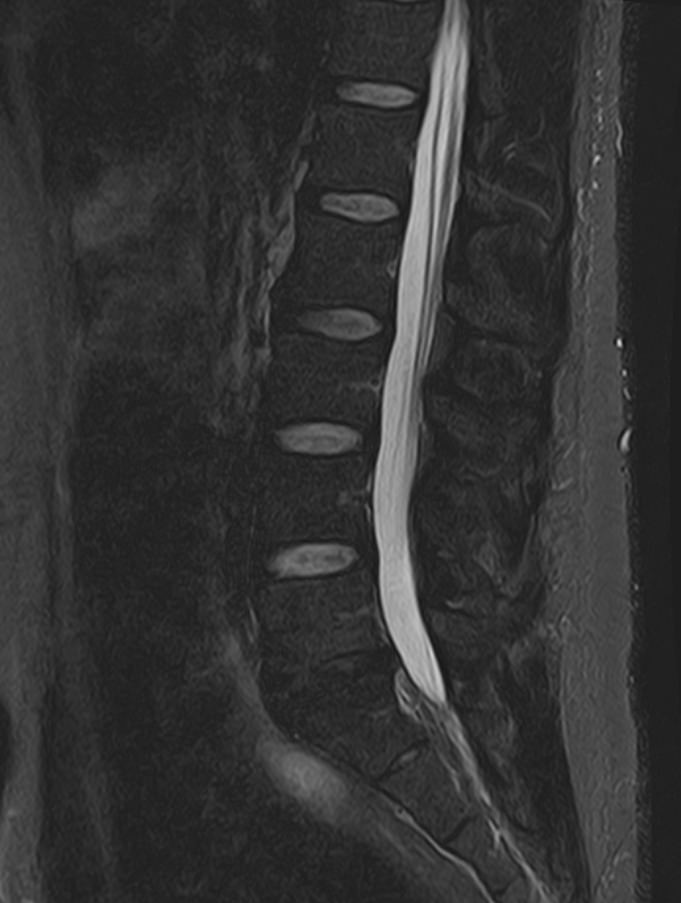

Наиболее точным и эффективным способом диагностики причин появления болей в нижней части спины является МРТ пояснично-крестцового отдела позвоночника. С помощью данного метода можно оценить состояние всех анатомических структур позвоночного столба на исследуемом уровне, безошибочно выявить происхождение болевого синдрома и назначить своевременное лечение.

В клинике «Доступная медицина» диагностика патологии нижней части спины осуществляется на высокотехнологичном оборудовании – новейшем высокопольном томографе TOSHIBA VANTAGE TITAN 1,5 Тесла, который обеспечивает высочайшее качество изображений, точность и достоверность полученных данных. Магнитно-резонансная томография осуществляется без применения ионизирующего излучения, поэтому является безопасным методом обследования и может применяться неоднократно.

Многим пациентам интересно, что показывает МРТ пояснично-крестцового отдела. Высокая детальность получаемых с помощью МР-диагностики изображений позволяет с точностью выявить следующие заболевания, локализующиеся в области поясничного отдела позвоночника:

• протрузии и грыжи межпозвонковых дисков;

• дегенеративные заболевания: остеохондроз, спондилез, спондилоартроз;

• последствия перенесенных травм, такие как компрессионные переломы, подвывихи и смещения позвонков;

• новообразования первичного и вторичного генеза;

воспалительные и деструктивные изменения позвонков и окружающих мягких тканей.